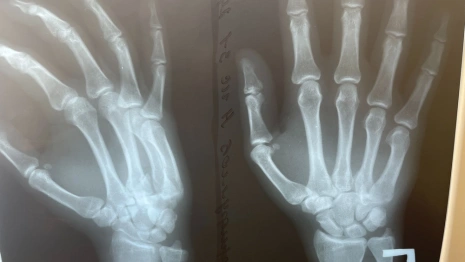

Медики установили диагноз – застарелый переломовывих основания 4-й пястной кости, застарелый вывих основания 5-й пястной кости правой кисти. Пациенту выполнили открытое вправление вывихов пястных костей, фиксация спицами. Сложность операции была обусловлена длительным промежутком времени, прошедшим от начала травмы.